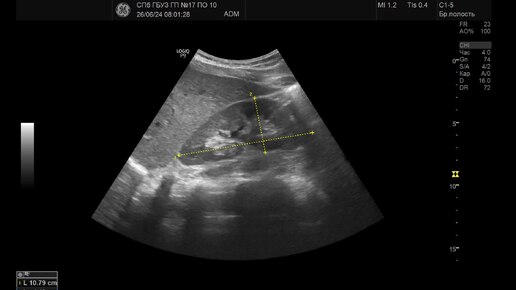

Ультразвуковая диагностика (УЗИ). Доктор Иогансен. Видеопримеры. Выпуск 87. Гипоплазия почки.